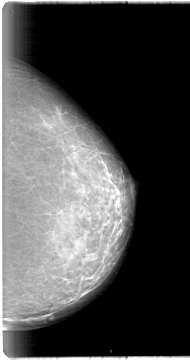

D_4001_1.LEFT_MLO

LEFT_CC LINES 5386 PIXELS_PER_LINE 2836 BITS_PER_PIXEL 12 RESOLUTION 43.5 NON_OVERLAY